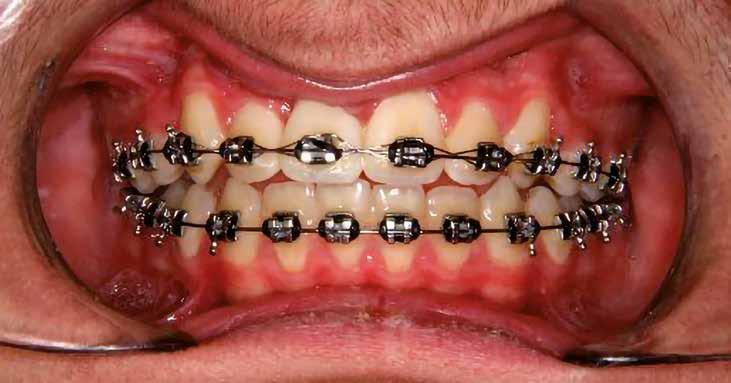

A vegyes fogazati kezelési célok a fogívek tágítása és a mandibula meziális irányú növekedésének a biztosítása volt. Fontos, hogy az ilyen típusú készülékeket nem csak éjszaka, hanem napközben is – amennyit csak lehet – hordani kell a minél hatékonyabb működés érdekében. A 18 hónapos első fázisú kezelésnek köszönhetően az alap kezelési célok megvalósultak, sikerült a class 1-es okklúziót beállítani (4-7. képek).

A második fázisú kezelés Pitts-21-es fix fogszabályozó készülék alkalmazásával történt meg. A Pitts elveknek megfelelően a kezelési célok a felső középső metszőfogak megfelelő pozicionálása, a 12 fogas (6-ostól – 6-osig) mosoly, az ideális íves lefutású mosolyvonal kialakítása, továbbá az okklúzió finomítása voltak. Mint mindig, a felső fogíven mosolyvonal beállító esztétikai pozicionálást (Smile Arc Protection - SAP) alkalmaztunk, a mes-

terséges harapásemelés pedig az alsó hatosokra, majd később a felső négyesekre került (8. kép). Az intermaxilláris elasztikus gumihúzás class-2-ess vektorú volt annak érdekében, hogy a disztálharapás korrekciója tökéletes legyen (9. kép). A harapást beállító elasztikus gumihúzásokat – mint minden kezelésnél –, ebben az esetben is folyamatosan, az egész kezelés alatt 24 órában (étkezések kivételével) viselte páciensünk.

A második Pitts-21 fix készülékes fázis ideje 16 hónap volt (10-12. képek)